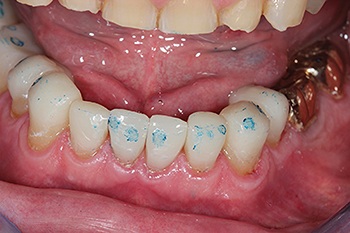

Shaw’s occlusal philosophy centers on a hands-on, iterative process. He builds, marks, and adjusts until all teeth contact evenly (Fig. 7). His goal is balanced group function with light canine guidance, while ensuring no single tooth bears excessive load.

Because the bicuspids sat buccal to their natural occluding position, he selectively added composite to opposing molars, improving functional stability without requiring orthodontic intervention.

Fig. 7: Occlusion adjustments